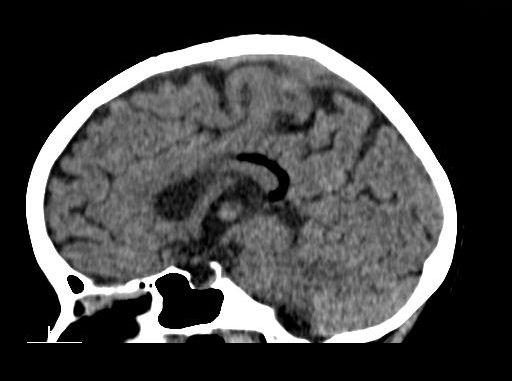

Case History: 7-year-old female with complaints of convulsions for one year.

Case History: 47-year-old male with headaches followed by generalized tonic-clonic convulsions.

Case History: 31-year-old female presents with complaints of headache and tinnitus.

48-year-old female presented with complaint of seizures.